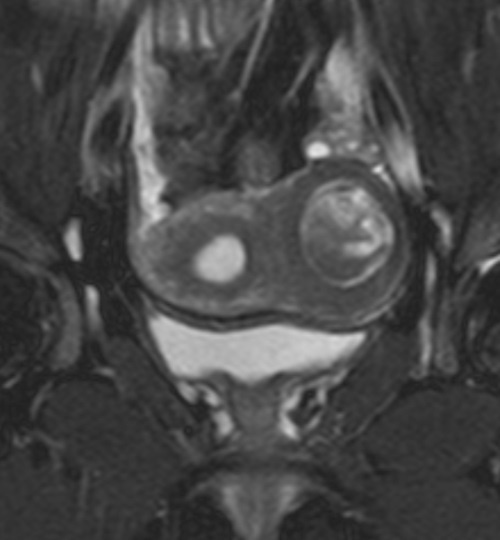

Пациентка 26 лет с клиникой остро возникших тазовых болей. Результаты УЗИ органов малого таза - тубоовариальный абсцесс, гидросальпинкс, внематочная беременность, эндометриоидная киста. По результатам УЗИ-данных и клинической картины пациентке выполнена диагностическая лапаротомия на основание которой выставлен диагноз - интрамуральная миома матки. После лапаротомия пациентка направлена на МРТ органов малого таза. На МР-изображениях в левом ребре матки определяется интрамуральное объемное образование округлой формы с жидкостным содержимым гипо- и гиперинтенсивного МР-сигнала на T2 и T2 SPIR ВИ (рис. А и Б соответственно) и однородно гиперинтенсивного сигнала на T1 и T1 с подавлением сигнала от жировой ткани ВИ (рис. В и Г соответственно). МР-картина соответствует миоме матки с внутриузловым кровоизлиянием.

На МР-изображениях в левом ребре матки определяется интрамуральное объемное образование округлой формы с жидкостным содержимым гипо- и гиперинтенсивного МР-сигнала на T2 и T2 SPIR ВИ (рис. А и Б соответственно) и однородно гиперинтенсивного сигнала на T1 и T1 с подавлением сигнала от жировой ткани ВИ (рис. В и Г соответственно). МР-картина соответствует миоме матки с внутриузловым кровоизлиянием.